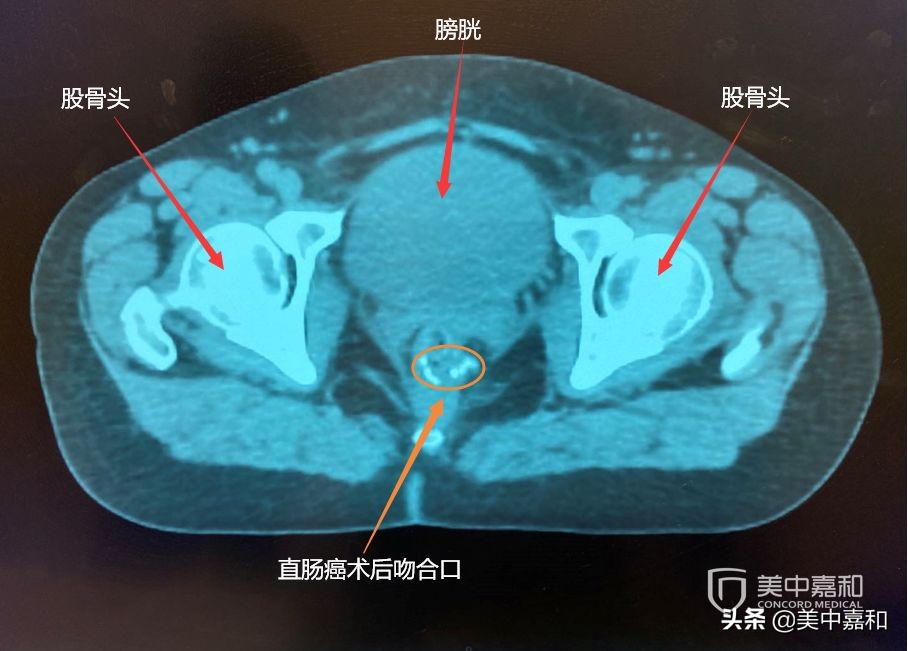

直肠癌术后图

刘女士于2017年,发现便血,去医院做肠镜检查,诊断为直肠癌。于七月份,做了超低位直肠癌前切除术(Dixon术),术后两年之内,遵医嘱进行复查。今年8月查CT,发现吻合口可能复发,进行手术,发现为癌前病变。刘女士和家属一直处于癌症复发的阴影中,希望寻求术后最佳治疗方案。一起来看美中嘉和国际多学科会诊专家们将给出怎样的治疗建议?

2019.8.5查CT示吻合口复发,2019.8.8行经肛门直肠吻合口肿物切除术,术中见距肛门2-3cm处相当原直肠吻合口左侧及后壁息肉样增生病变,最大范围1.5cm,予以尽可能切除。术后病理:锯齿状腺瘤伴高级别上皮内瘤变。

文章审较:王斌医生 影像供图:温阿明医生